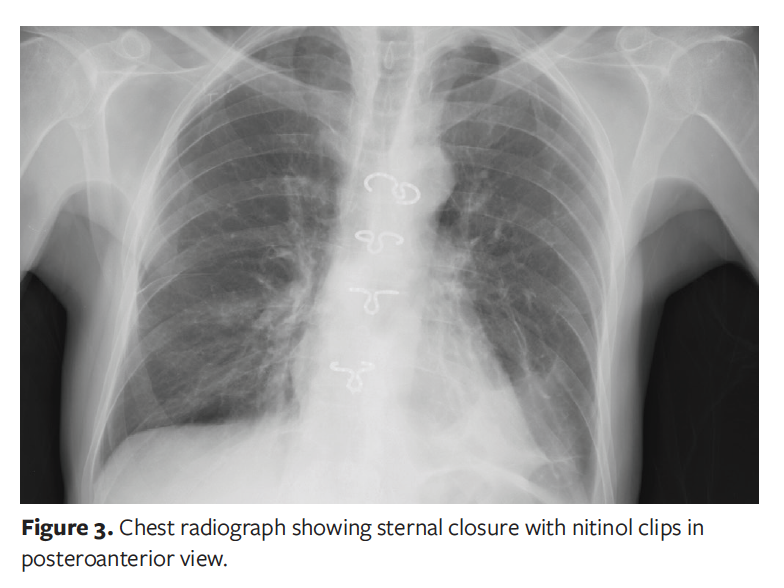

Application of nitinol clips involved insertion of 3 or 4 clips in select intercostal spaces. Electrocautery was used to create a tunnel through each space in which a clip would be positioned, taking care not to injure the internal thoracic arteries. The distance between the 2 intercostal spaces was then measured to choose the clip size. The clips were cooled with ice to make them deformable and easy to place, set on special forceps, and inserted in the intercostal spaces. Finally, the clips were heated with warm water to return them to their original consistency. A chest radiograph showing nitinol clips in situ is seen in Figure 3.